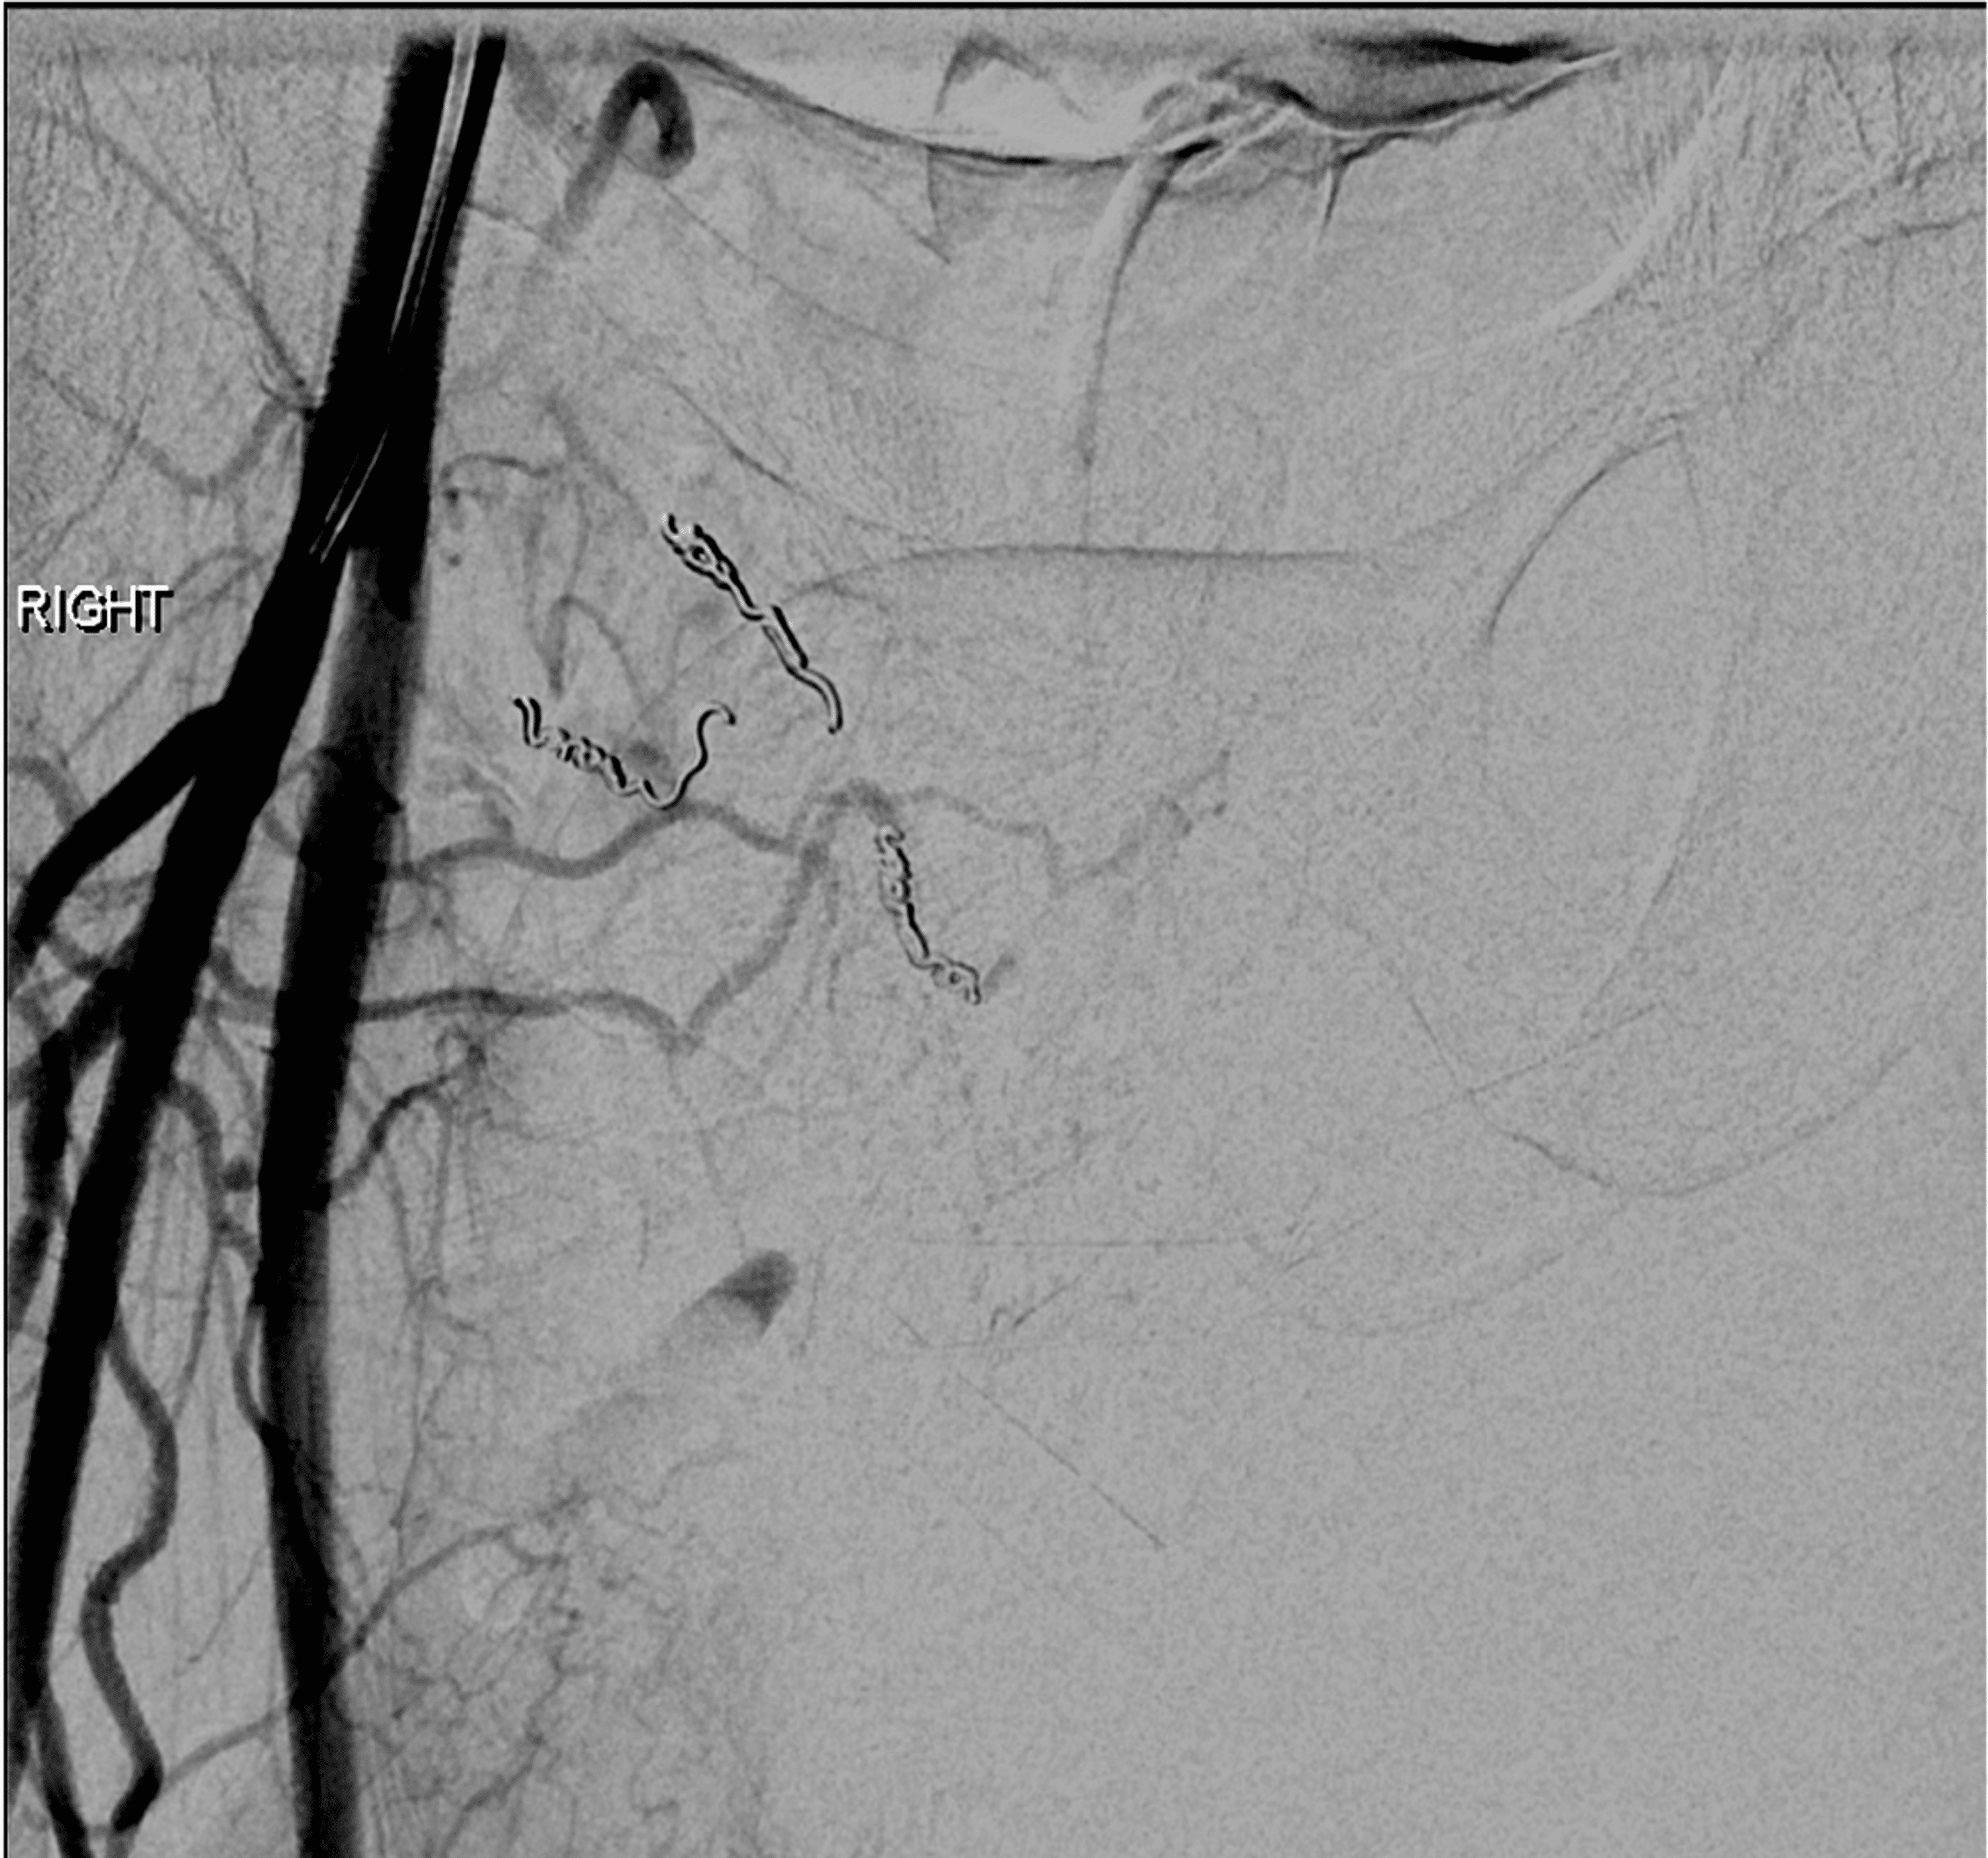

(PDF) Coil embolization of a thoracic aorta hematoma with branch artery Coil Embolization Of Hematoma embolization procedures for extracranial disease in the head and neck region are mostly performed for intractable epistaxis. middle meningeal artery embolization (mmae) has shown promise as an alternative treatment for chronic. sometimes coils are used with stents to prevent the coils from moving out of the aneurysm. Embolization of the middle meningeal artery (mma) has emerged as. Coil Embolization Of Hematoma.